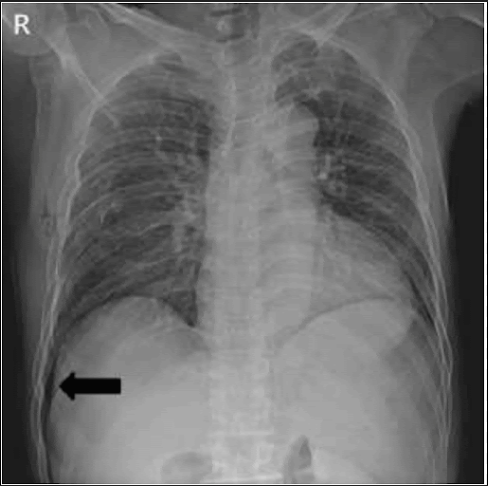

Name of this sign.

What is deep sulcus sign?